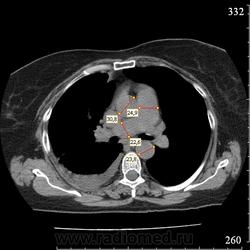

Еще один случай диагностики ТЭЛА методом КТ-ангиографии у женщины 59 лет. Основная клиническая жалоба - выраженная одышка. Определяется: полный дефект наполнения в системе правой ЛА (бифукация и нижнедолевая), неполный дефект наполнения в левой ЛА (нижнедолевая), пристеночные тромбы по задней стенке в области бифуркации обеих легочных артерий. Инфаркт (массивное кровоизлияние) нижней доли правого легкого. Правосторонний малый (120см3) гидроторакс. Несмотря на выраженные тромбы, поперечники легочных артерий - в пределах нормы.; на нативной (безконтрастной) КТ - тромбы не видны. Несмотря на почти полный дефект наполнения в левой нижнедолевой артерии, изменений в легочной ткани левого легкого нет. Также приводится топограмма, как вариант, приближенный к рутинной рентгенограмме